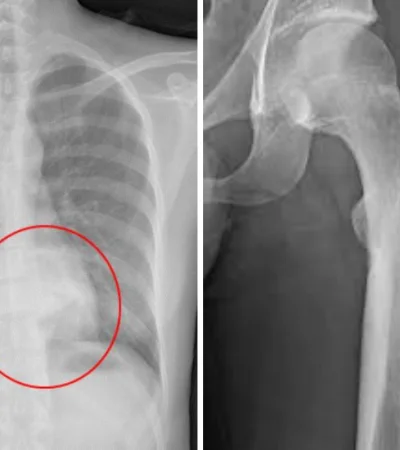

Imagen ilustrativa de osteoblastomas detectados.

Imagen ilustrativa de osteoblastomas detectados. -

Según Niewiadomski, los primeros síntomas suelen ser el dolor óseo persistente, inflamación y, en algunos casos, fracturas. Ante estos indicios, es clave avanzar con estudios de diagnóstico: "Empieza con una radiografía, se ve algo dudoso, se pide una tomografía o una resonancia magnética y eventualmente se hace una biopsia para determinar de qué se trata".

De acuerdo con la Biblioteca Nacional de Medicina de Estados Unidos, el osteoblastoma es un tumor benigno que forma hueso y suele aparecer en la columna vertebral y el sacro, aunque también puede manifestarse en otras áreas como la mandíbula o los huesos largos.